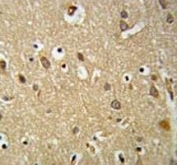

IGF1R antibody IHC analysis in formalin fixed and paraffin embedded brain tissue.